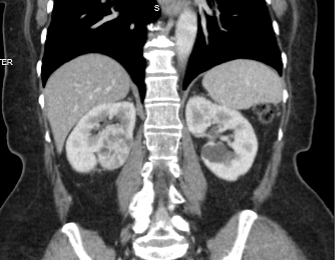

The patient’s data were input into RFAN-ML (Figure 2), which estimated that the eGFR after partial nephrectomy would be 84 ml/min verus 58 ml/min after radical nephrectomy. We explained that preserving this amount of renal function may translate to better overall health, given the links between kidney function and cardiovascular outcomes.7

Figure 2. Deployment of RFAN-ML, a simple application to estimate renal function after partial or radical nephrectomy. Source: NYU Langone Health

With a better understanding of the magnitude of the benefit of partial nephrectomy on renal function, the patient elected for this approach. She underwent a successful partial nephrectomy.